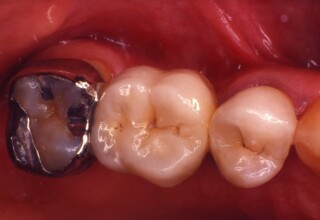

Αποκατάσταση Οπίσθιου Απονευρωμένου Δοντιού με Ανασύσταση Σύνθετης Ρητίνης

Η συνήθης αποκατάσταση ενός απονευρωμένου οπισθίου δοντιού είναι με μια στεφάνη. Ο κύριος λόγος είναι η προληπτική προστασία από κάταγμα και την επακόλουθη εξαγωγή. Σε πολύ συγκεκριμένες περιπτώσεις όπου εξειδικευμένα κριτήρια (κυρίως η ποσότητα της εναπομείνουσας οδοντικής ουσίας) ικανοποιούνται ή όταν η οικονομική δυνατότητα του ασθενή το επιβάλει, μια εκτεταμένη ανασύσταση συνθέτης ρητίνης μπορεί ν’αποκαταστήσει την αισθητική και λειτουργικότητα του δοντιού.

Αποκατάσταση Ραγισμένου Γομφίου με σφράγισμα Σύνθετης Ρητίνης

Τα ραγισμένα δόντια αποτελούν μια πρόκληση για την επανορθωτική οδοντιατρική από την άποψη της δυσκολίας της αποκατάστασης(συνήθως μεγάλα σφραγίσματα) άλλα κυρίως από τα προληπτικά μετρά που πρέπει να παρθούν για να αποφευχθεί ένα πλήρες κάταγμα. Η ακόλουθη περίπτωση παρουσιάζει την απλούστερη προσέγγιση της άμεσης συγκολλούμενης αποκατάστασης από σύνθετη ρητίνη. Βασίζεται στο σκεπτικό ενός συγκολούμμενου σφραγίσματος που «κρατάει» τα εναπομείναντα οδοντικά τμήματα «ενωμένα». Ο συγκεκριμένος γομφίος παρέμεινε ακέραιος για δυο χρονιά, οπότε χρειάστηκε απονεύρωση γιατί νεκρώθηκε και κατόπιν τοποθετήθηκε στεφάνη για αυξημένη προστασία.